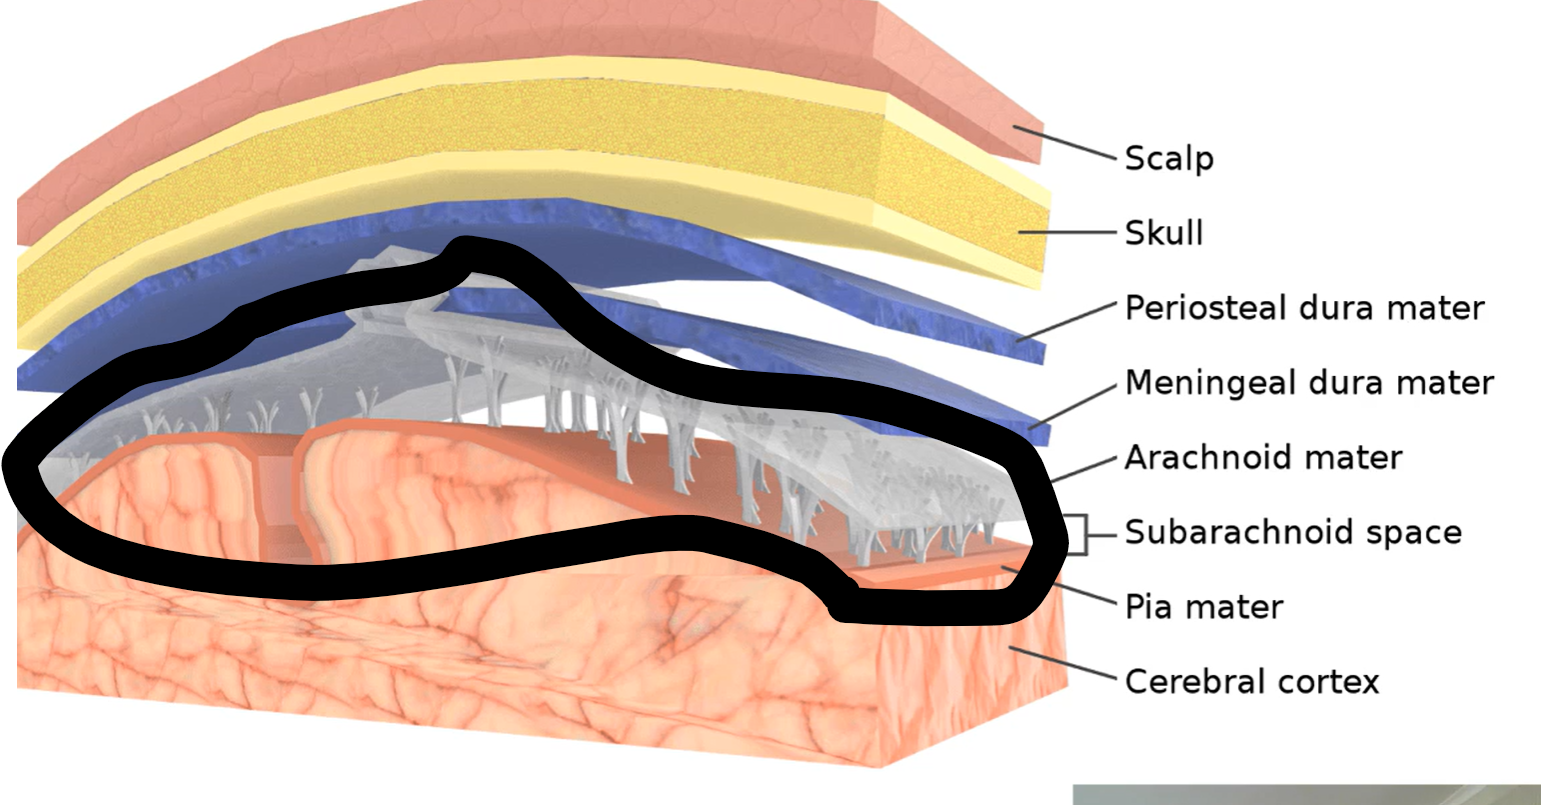

How many layers of meninges

3

Layer of meninges from superficial to deep

Dura mater

Arachnoid mater

Pia mater

What are the two layers of dura mater?

Periosteal dura mater

Meningeal dura mater

What does the pia mater follow?

Sulci and gyri

What does subdural space separate?

Dura mater and arachnoid mater

What does subarachnoid space separate?

Arachnoid mater and pia mater

What lies between meningeal dura mater and periosteal dura mater?

Dural venous sinuses

What does CSF flow back into dural venous sinuses by?

Arachnoid granulations

What are those grey projections called?

Arachnoid trabeculae